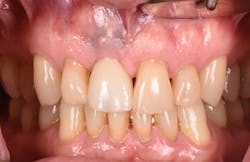

Figure 17: Patient presented with buccal vestibule swelling and complaining of pain. Swelling is visible and palpable with discoloration of the soft tissue.

Figure 18: Pre-op radiograph shows retrograde peri-implantitis possibly from previous periapical pathology.

Figure 19: Immediately after incisions and raising a full-thickness flap, suppuration was noted on the apex area of the implant.

Figure 20: An osteotomy was done to access apical area of implant No. 8 utilizing the Er:YAG laser at 20 pps/70 mJ. The then-exposed area was irradiated using a combination of detoxification and biostimulation of the bone and implant to prepare the area to receive a bone graft.

Figure 21: After mechanical debridement and surface detoxification

The Er:YAG laser has been more recently known for its ability to remove calculus from a titanium implant surface as well as detoxification (figures 17–21).9 Many authors have shown the laser’s use in combination with mechanical debridement to be superior when using a regenerative approach to treat peri-implant diseases (figures 22–26).10 A particular feature of this laser is the microexplosions that occur when the laser energy is absorbed by water. The volume of these explosions suddenly expand up to 1,000 times, covering more surface area of a titanium implant. It has been found that both contaminated debris and the contaminated oxide layer are removed as a result of these microexplosions.11